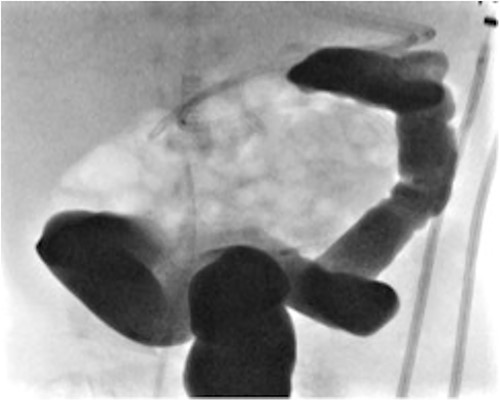

A female infant born at 37 weeks (birth weight 1.9 kg) and a neonatal course complicated by significant respiratory distress and bilateral pneumothoraces, also found to have a hypoplastic aortic arch on echocardiogram. On day 4 of life, she underwent an aortic arch repair (bypass time - 2 h 44 min, clamp time 24 min) and the chest was left open. Inotropes were required post operatively (3 days of vasopressin, 4 days of dopamine, and 19 days of milrinone). At 4 weeks of age, she underwent chest closure. At 5 weeks of age, she developed feed intolerance, abdominal distension, and bilious nasogastric aspirates. She was treated with bowel rest and intravenous antibiotics for 1 week. At 9 weeks of age, she was investigated for ongoing inability to advance feed and found to have distal transverse colonic obstruction (Fig. 4). At laparoscopy, a dilated proximal transverse colon was encountered with a clear transition point to collapsed distal colon. However, the serosal surface was intact and uninterrupted. An enterotomy made at the transition point revealing complete occlusion of the lumen by a mucosal web consistent with an acquired colonic atresia. A transverse loop colostomy was fashioned at this point and the baby recovered well. She is awaiting colostomy closure. A diagnosis of Turner’s syndrome was later confirmed. We have included a summary of cases 1, 2, and 3 in Table 1.

Contrast enema for case 3 showing complete failure of passage of contrast into distal transverse colon.